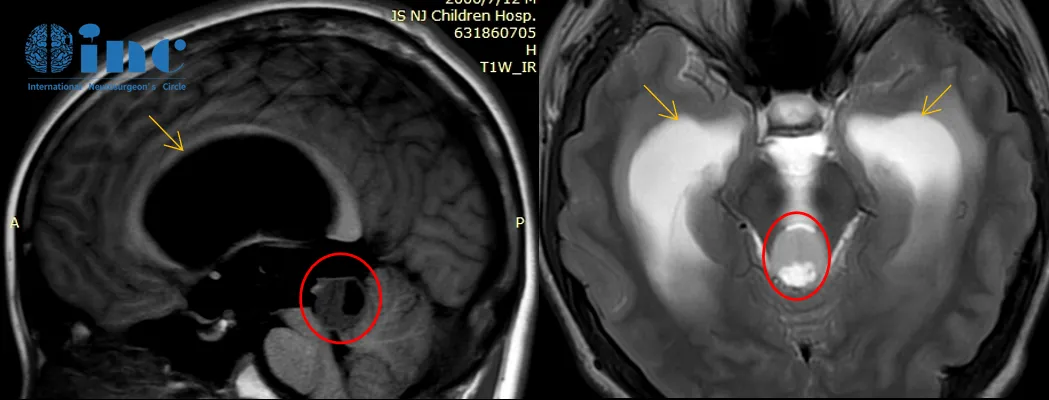

2018年2月头颅核磁检查:脑干-中脑顶盖占位伴梗阻性脑积水

2020年8月头颅核磁检查:肿瘤较前增大,脑积水较前明显加重

2020年的影像检查发现脑干-中脑顶盖占位伴幕上脑室扩张积水,较2018年的影像检查显示肿瘤有明显强化生长迹象。

手术经正中幕下小脑上入路手术,术中使用神经电生理监测和MRI辅助,保证神经功能、重要脑组织和大脑静脉不受损伤。由于肿瘤基底部和脑干关系密切、紧邻小脑,教授在保全患者正常功能神经和脑干等重要脑组织的前提下,完成肿瘤近全切手术,病理结果为脑干-中脑顶盖毛细胞型星形细胞瘤,这是一种预后较好的胶质瘤,通常手术全切或近全切除可获得良好预后。

术后3个月回访时,小永复查MRI表明肿瘤已经很好地切除了。由于术前伴有长期的梗阻性脑积水,导致脑室扩大,脑积水吸收不良仍然存在,还需要一段时间的康复治疗。但患者的整体状态已经恢复得很好了,可以逐步回归正常的生活。术后1年半,小永不仅已经回归正常生活和学习,还以优异成绩考入名校。